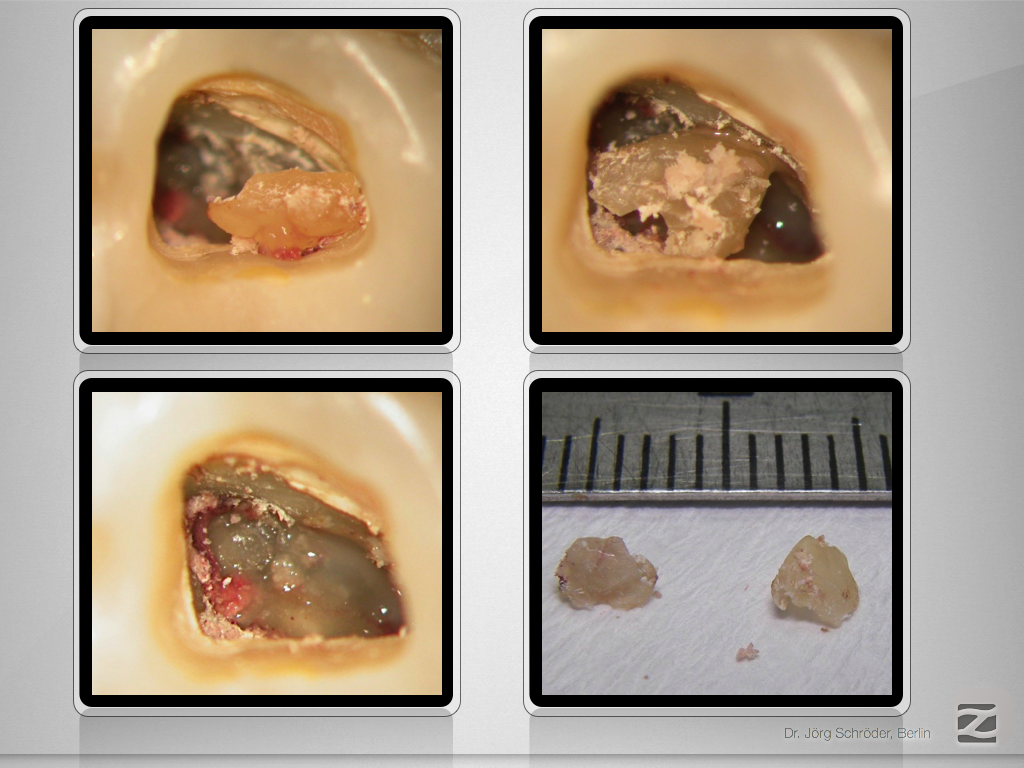

Mutter aller Dentikel